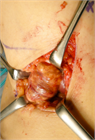

1. 関節水腫の原因となる疾患を、貯留した関節液の性状から、1)非炎症性2)炎症性3)化膿性4)血性の4グループから原因疾患を分類して考える(推奨度2)

1. その原因として、変性疾患、リウマチ性疾患、化膿性疾患、腫瘍性疾患、それに外傷などがある(推奨度2)